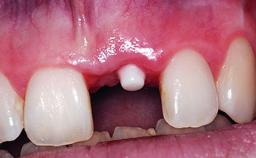

A healthy 37-year-old female patient was referred for a consultation on the replacement of missing tooth 21 with an implant-supported restoration. She stated that several years previously the tooth had been traumatically avulsed following a motor vehicle accident. The tooth was replaced with a three-unit fixed partial denture (FPD) immediately afterwards. Over time, she became disillusioned with the FPD and looked for a different option, including orthodontic therapy. She presented still in her orthodontic appliances, with the pontic sectioned free from the FPD but attached to the archwire. Her orthodontist felt that orthodontic treatment had been successfully completed, but nevertheless referred her before removing the appliances in case adjustments were necessary.

| Loading Protocol | Conventional or early |

| Interim Prosthesis during Healing | Fixed Fixed |